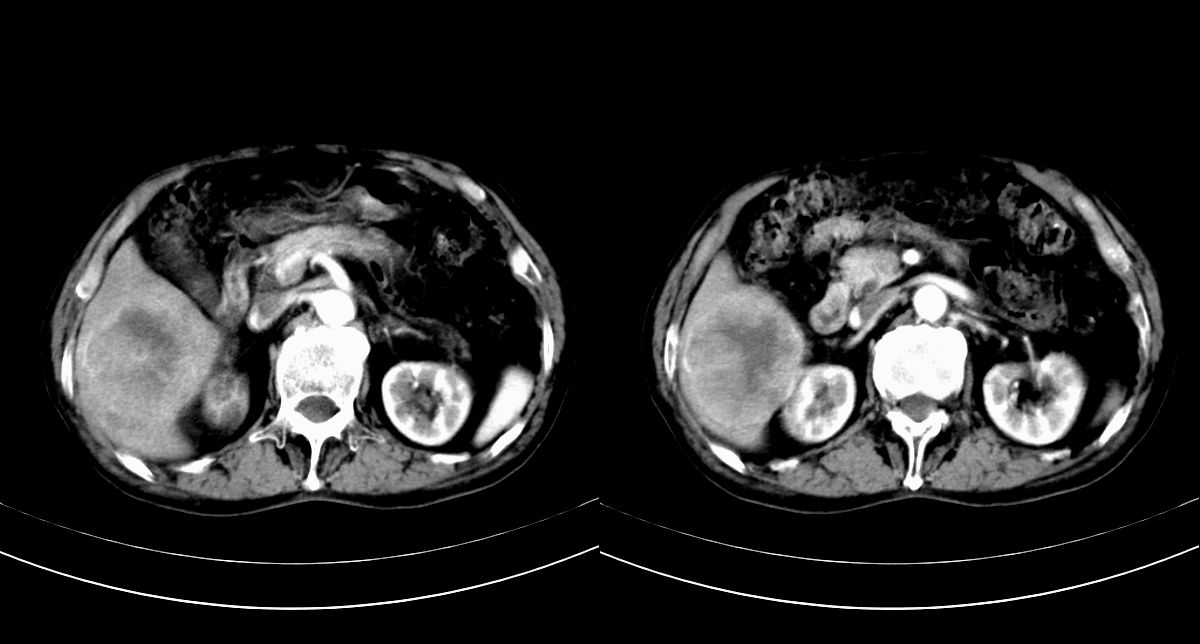

男,79y,无不适。体检发现肝脏占位。

肝内多发低密度结节,增强动脉期明显强化,门脉期逐渐下降,内有液化坏死区。

诊断:

肝细胞癌(结节型)

鉴别:肝转移癌。

肝内多发低密度结节灶,增强动脉期明显不规则环状强化,;门脉期逐渐下降,肿瘤壁厚薄不一,内有坏死液化区。

诊断:肝转移癌可能

鉴别:1原发性肝癌(强化方式符合,建议查afp)

2肝脓肿(无临床病史支持)